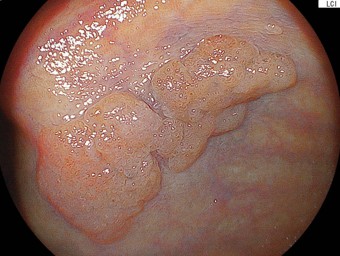

症例1:他院から日帰り内視鏡切除目的で紹介された症例。盲腸に20mm大の平坦な病変を認めます。LST-NG(flat-elevated type)に分類されます。拡大内視鏡では「がん」を疑うVI型ピットパターンを認めませんでした。腺腫病変と考えました。5mm程度の近傍に憩室を合併しております。無条件で内視鏡的粘膜下層剥離術(ESD)を適応している施設も多いかと思います。しかし、このような病変は、線維化(:粘膜下層の線維が密に増生していること、しばしば内視鏡治療の困難性を引き起こします)がなければESDの適応などないのです。当院では、内視鏡的粘膜切除術(EMR)により平坦な病変であっても30mm弱程度までは適応としていることが多いです。最終病理診断:高異型度腺腫で切除断端陰性で治癒切除(ちゆせつじょ:取り切れて治っていること)でした。術後も偶発症を認めませんでした。